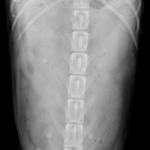

1週間前に団子を串ごと誤飲した可能性があるワンコが急にぐったりしているとのこと。すぐに地元の救急病院を受診すると異物による胃穿孔が疑われました。外科的な摘出と腹膜炎によるクリティカルケアが予想されたため紹介来院しました。開腹後、竹串による胃穿孔が確定されました。腹膜炎も同時に起こっています。穿孔創を封鎖し、腹腔洗浄とドレインの設置を行いました。幸いにも48時間後に食欲が出て退院となりました。愛犬が竹串を誤飲してしまったら、命に関わる事態に発展する可能性もあるため、早めに内視鏡による摘出をお勧めします。このような異物を発見するためにはエックス線よりも超音波検査が非常に有効です。